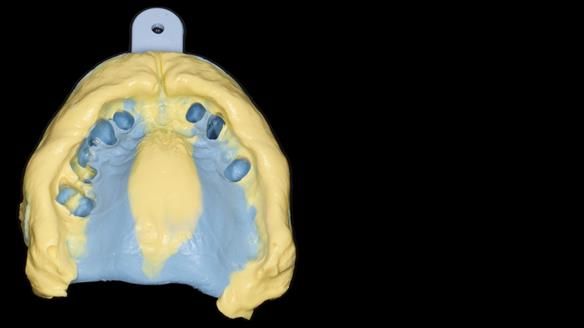

She had previously suffered from generalised periodontitis – stage IV, grade C, currently stable, with reduced attachment across the upper arch.

By the time she came to me, her periodontal condition was stable — but the aesthetics in the upper jaw were very poor.

We provided her with an immediate upper denture (Mk 1), followed by a definitive metal-based upper denture (Mk 2). A lower removable partial denture was discussed, to be made only if needed once the upper treatment was complete. However, at review, this wasn’t necessary — Adnana had excellent neuromuscular control and function, even with a shortened dental arch (SDA).

Rowan, Sam Hesketh and Chris Hesketh provided the stunning technical work. I am very lucky to have them.